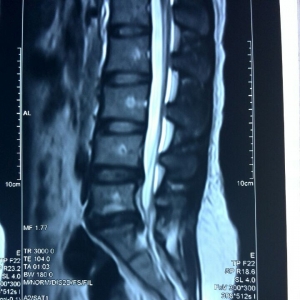

病      情:重度腰椎间盘突出症,腰5骶1椎间盘脱出,椎管狭窄,下肢放射性疼痛,全足麻木,轮椅来诊住院。患者拒绝手术,要求我科弧刃针刀治疗。

治      疗:2014年11月24日18:30,河南省中医院疼痛科学习例会上,王学昌主任给予患者现场学术操作表演,视频如上。术后明显改善,今晨大查房足部内侧麻木消失,仅外侧稍麻木,腰腿疼痛症状亦明显改善,患者很是满意。

分      析:患者并非单纯腰椎间盘脱出症,而是还伴有右侧踝管综合征,河南省中医院疼痛科采用国家专利技术,弧刃针刀松解踝管即可解除足部麻木症状,无需髓核摘除手术治疗。

在十余年临床工作中,王学昌主任认为,绝大多数的腰椎间盘突出症患者、或者颈椎病患者都无需微创或手术治疗,一般采用非手术疗法,特别是弧刃针刀疗法即可解决。即使那些严重腰椎间盘脱出患者,部分脱出的椎间盘也有吸收的病案报道。只有那些经过正规足程,3-6个月的非手术治疗、特别是弧刃针刀治疗无效的患者,我们才应考虑微创或手术治疗。